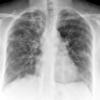

COPD

Date: 06/06/2004

Views: 14198